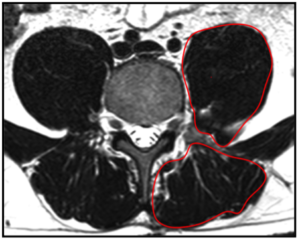

Die tiefliegenden Rückenmuskeln, oftmals auch als autochthon („ortsständig“) bezeichnet, haben eine Schlüsselfunktion bei der Aufrichtung und Stabilisierung der Wirbelsäule [Wagner et al., 2005]. Vor allem die Muskeln des sogenannten „medialen Stranges“ sind segmental angeordnet und daher für die segmentale Stabilisierung und Hauptkontrolle der Wirbelsäule verantwortlich (siehe Abb. 1) [Creze et al., 2015; Deng et al. 2015]. Unterstützt werden diese Muskeln von einem komplexen System aus Faszien. Gut trainierte Muskeln erhöhen diese fasziale Spannung und gewährleisten eine systemische Stabilität [Willard et al., 2012].

Abb.1: Lateraler (links) und medialer (rechts) Strang der autochthonen Rückenmuskulatur